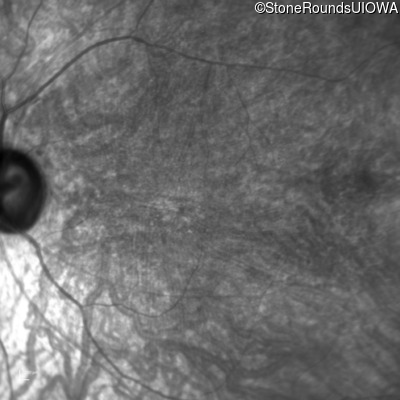

Infrared Fundus Photograph - Right - 20/100 -1 sc

Exemplar

Infrared Fundus Photograph - Left - 20/100 -2 sc